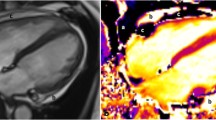

Spatio-temporal phase unwrapping [15] was performed within the contoured area to remove phase aliasing, and the phase data from the three encoding directions were combined to create 3D Eulerian displacement fields. Figure 1 illustrates contoured cine DENSE magnitude and phase-unwrapped images and the corresponding 3D displacement fields at end systole for a single short-axis slice.

A single short axis slice of the 3D cine DENSE data at mid systole. (a) DENSE magnitude image illustrating the myocardial mid-line for the RV (green dotted line). (b, c, d) DENSE unwrapped phase images encoded for motion in the x, y and z directions, respectively. (e) Corresponding 3D DENSE displacement field. Red lines correspond to epicardial surfaces and blue lines correspond to endocardial surfaces.

There are typically too few transmural pixels spanning the RV to acquire a full 3D strain tensor, so 2D strain at the RV mid-wall surface was calculated. The mid-line between epicardial and endocardial contours was used to produce tissue tracking seed points, which were spaced at pixel-distance intervals on the first cardiac phase. The mid-line contours were spatially smoothed within and across partitions using 4th order polynomial fitting to ensure a continuous RV surface. An example of the RV mid-line points is shown in green in Figure 1(a).